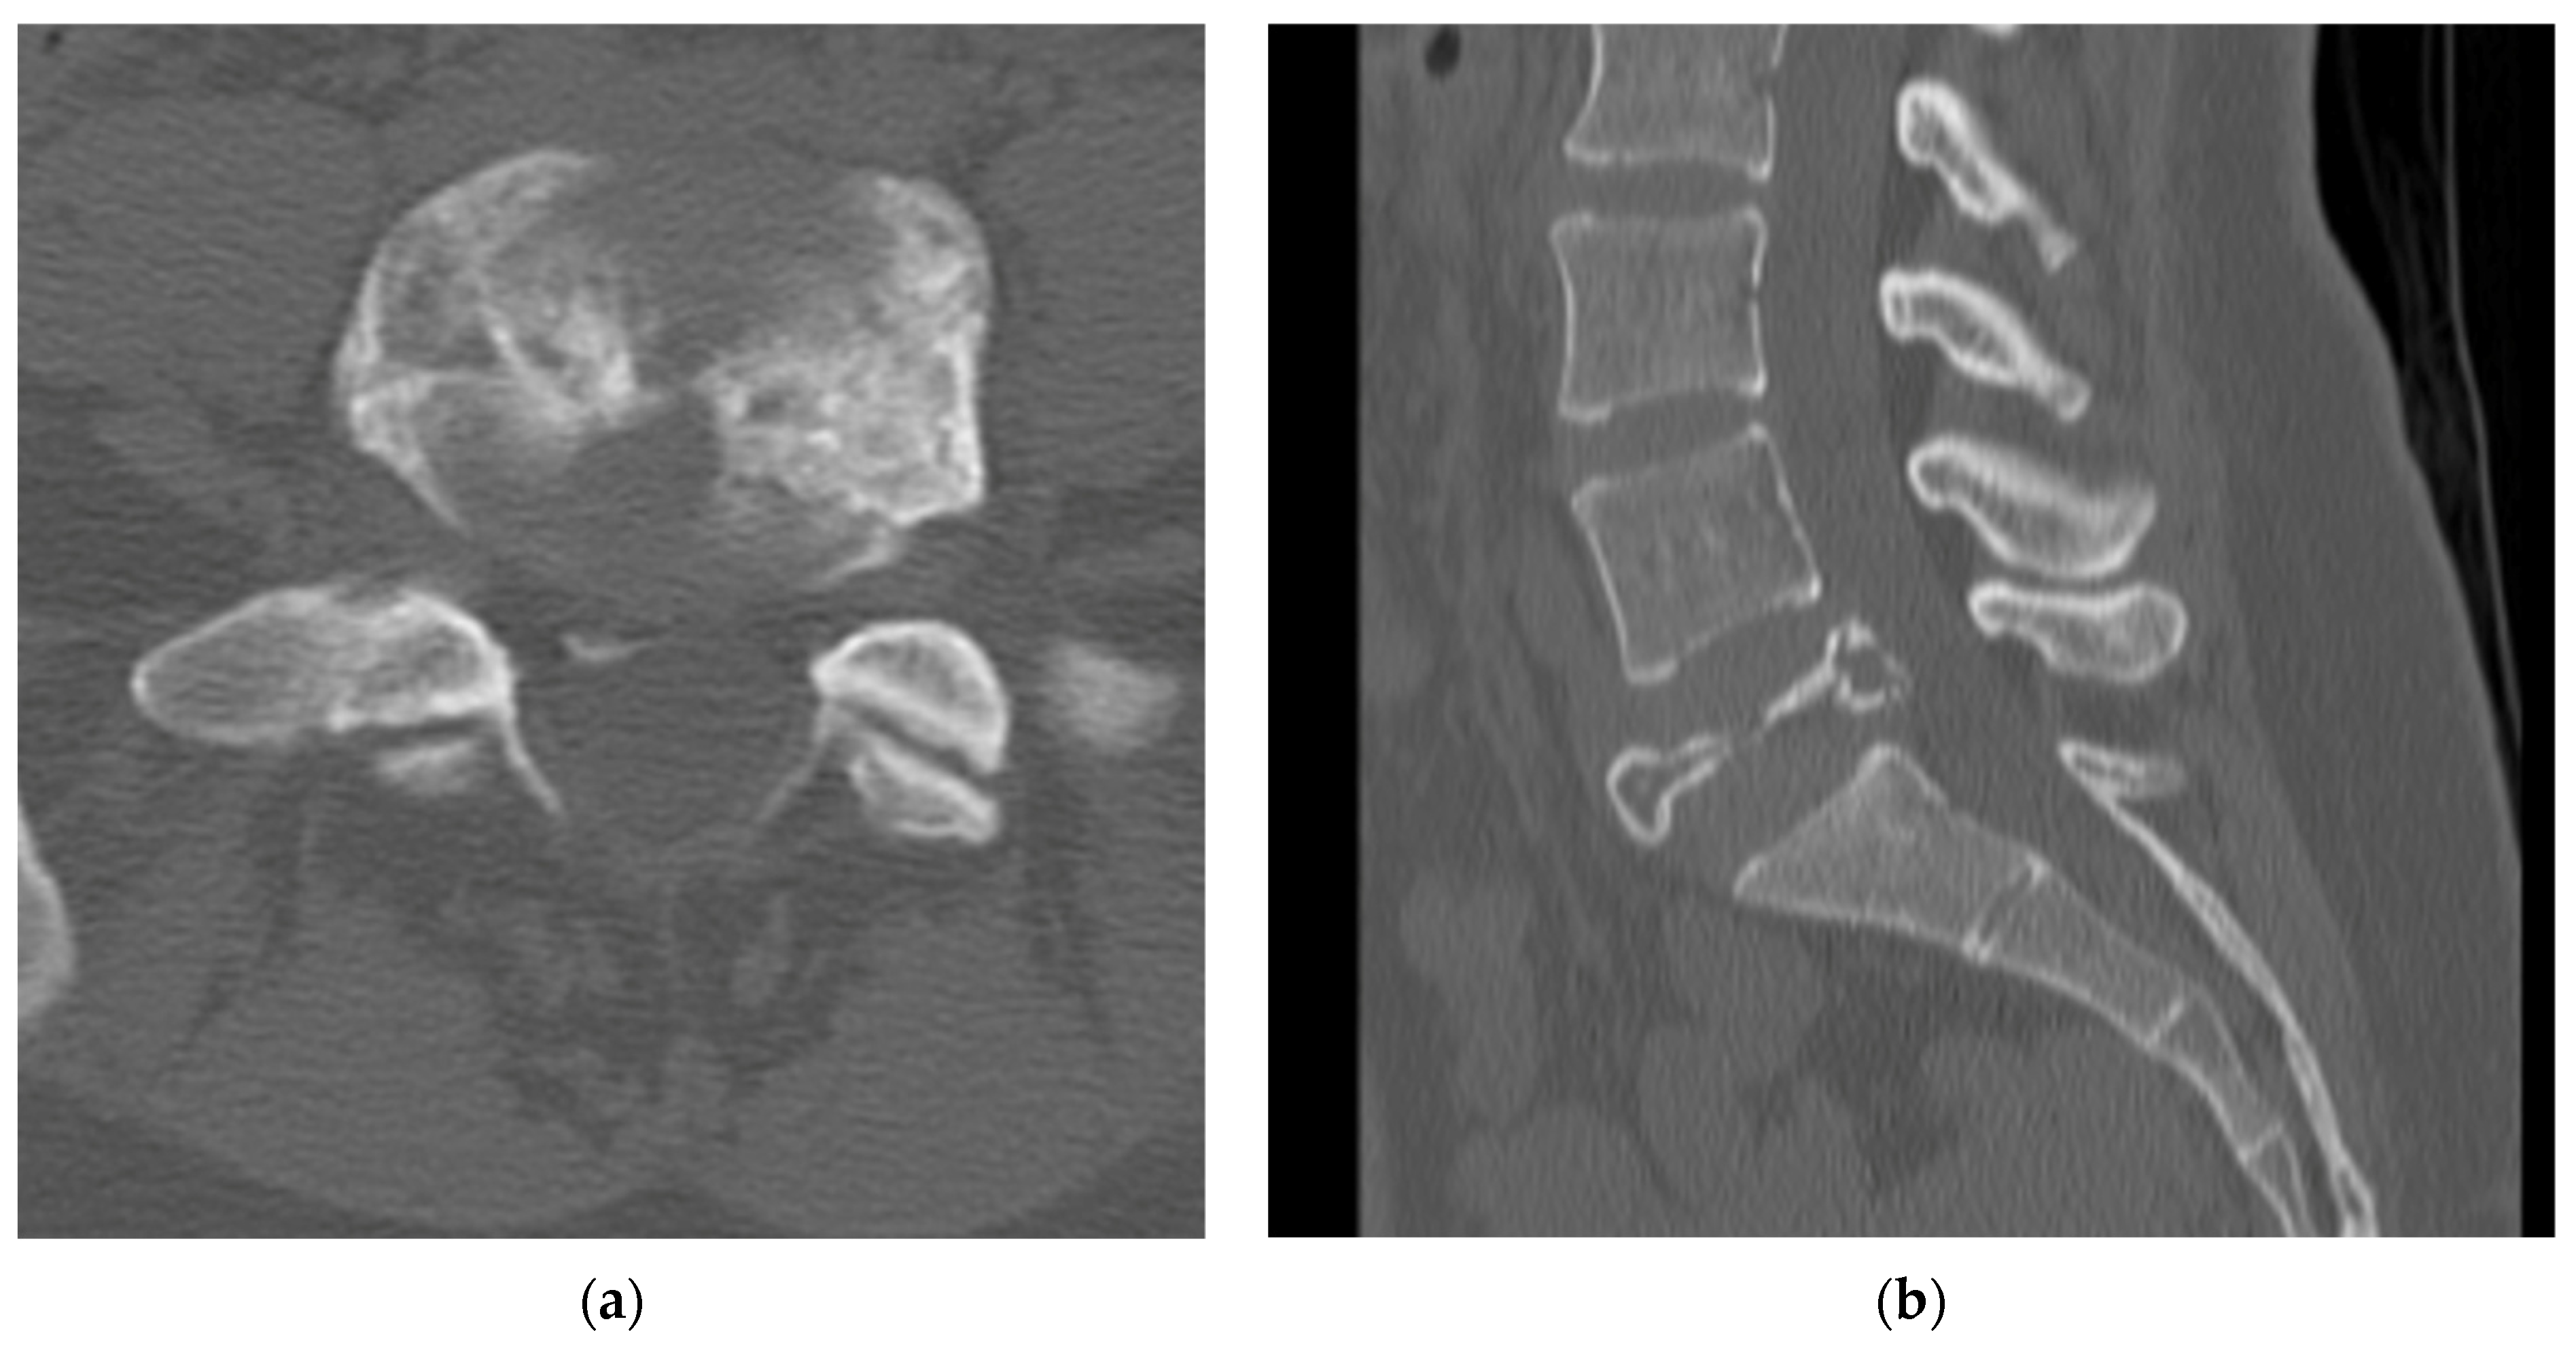

4.2.4. Computerized Tomography Scan

4.5.3. Secondary Aneurysmal Bone Cysts